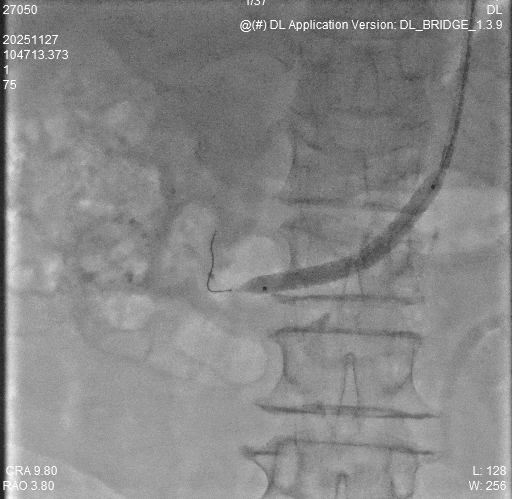

2.导管配合0.035导丝进入腹主动脉下端,造影示:腹主动脉走形迂曲,血流通畅,右肾动脉主干起始段重度狭窄>90%,远端及分支显影浅淡。

3.换鞘管后引入导丝及导管置于右肾动脉开口处,冒烟确定右肾动脉位置,换0.014in及0.018in导丝通过狭窄段后置于右肾动脉远端分支,经导丝引入3*40mmPTA快速交换球囊预扩狭窄段。

4.导丝支撑下交换引入CWB60605L-18震波球囊扩张右肾动脉狭窄段,完毕后复查造影示右肾动脉通畅,血管残余狭窄<20%,扩张效果满意,术毕。